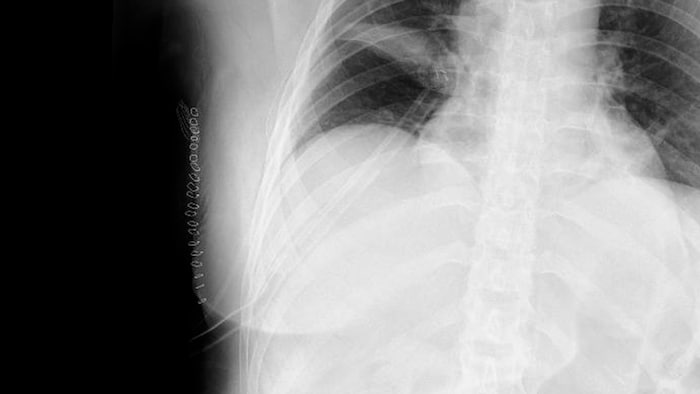

According to her lawyer, Karin Prutsch-Lang, the woman had already been admitted to LKH Graz II in September 2024 with fever, chills, and severe weakness. Tests showed inflammation but no tumor. Nevertheless, a tissue sample was taken. The diagnosis later came back as adenocarcinoma – lung cancer.

The doctors recommended immediate surgery at a private clinic, even though there were other findings that indicated only inflammation, not a tumor. Nevertheless, part of the lung was removed shortly thereafter. After the procedure, it turned out that the patient was completely healthy. In reality, she never had cancer.

The consequences for the woman are serious. She now suffers from a large scar with numbness, limited resilience, and severe anxiety. A 17-centimeter-long scar now adorns her chest, and she needs help to cope with her everyday life.